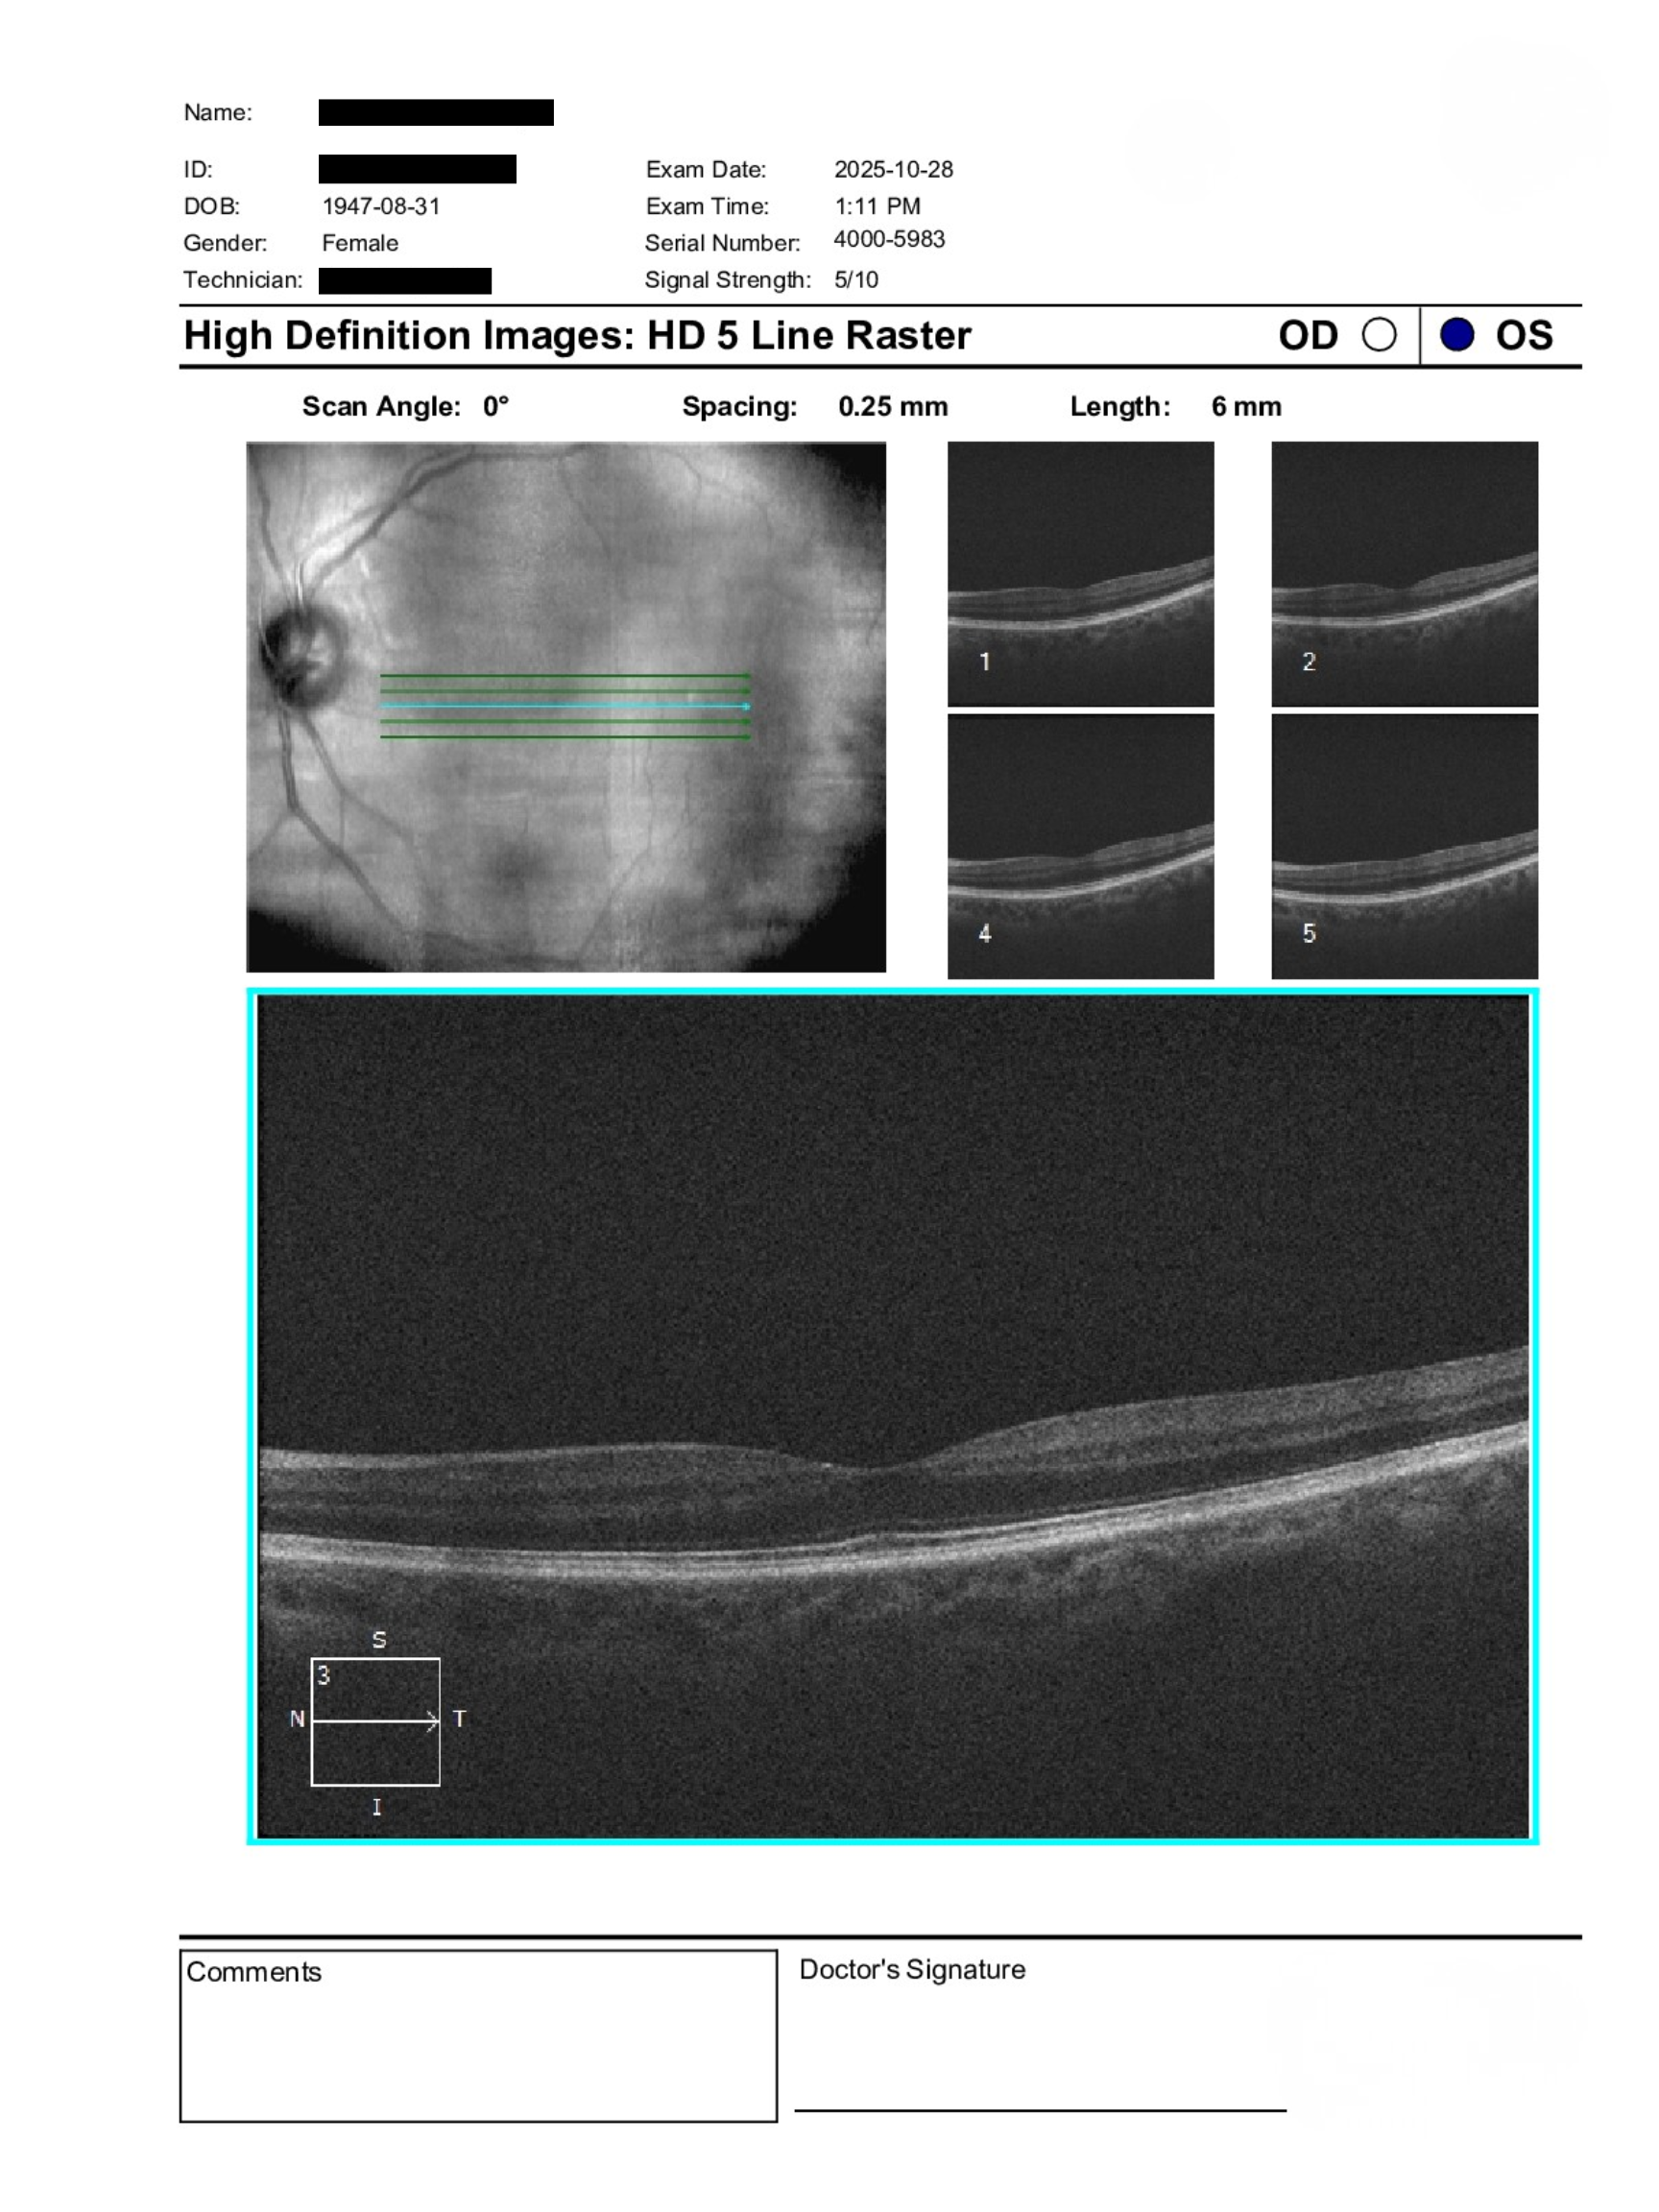

A 78-year-old patient with diabetes presented for assessment. BCVA was not documented. IOPs were not recorded. Anterior segment exam showed mild nuclear sclerosis in both eyes. Posterior segment exam revealed retinal hemorrhages in the right eye and none in the left. The differential included diabetic retinopathy versus retinal vein occlusion.

The findings in the right eye are concerning for a retinal vein occlusion, which remains high on the differential. However, the absence of optociliary shunt vessels and limited venous tortuosity raises concern for ocular ischemic syndrome. Further diagnostic evaluation is required to distinguish between these possibilities.

Urgent in-person assessment is recommended, including intravenous fluorescein angiography and carotid ultrasound. Timely referral is important to guide diagnosis and management.